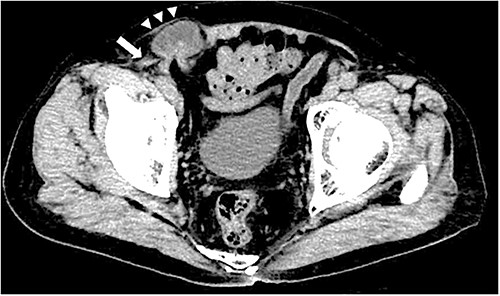

A 79-year-old male patient with a medical history of right inguinal hernia presented to the emergency department with right inguinal swelling and pain. We found the inguinal swelling, which extended toward the head, to be atypical. In addition, contrast-enhanced computed tomography (CT) scan revealed that a portion of the small intestine was incarcerated between the internal and external oblique muscles, and the hernia contents had prolapsed cranially from the hernial orifice. Furthermore, the sagittal view revealed that the contents of the hernia had prolapsed ventrally and not along the spermatic cord (Figs 1 and 2). Therefore, we diagnosed it as a right interparietal inguinal hernia, and laparoscopic hernia repair was planned. Owing to the fact that the manipulative reduction was difficult, we planned to release the incarceration first.

Contrast-enhanced CT scan; an incarcerated bowel was observed in the right inguinal region; the small bowel was incarcerated between internal and external oblique muscles; the white arrow indicates the internal oblique muscle, and the white triangles indicate the external oblique muscle.